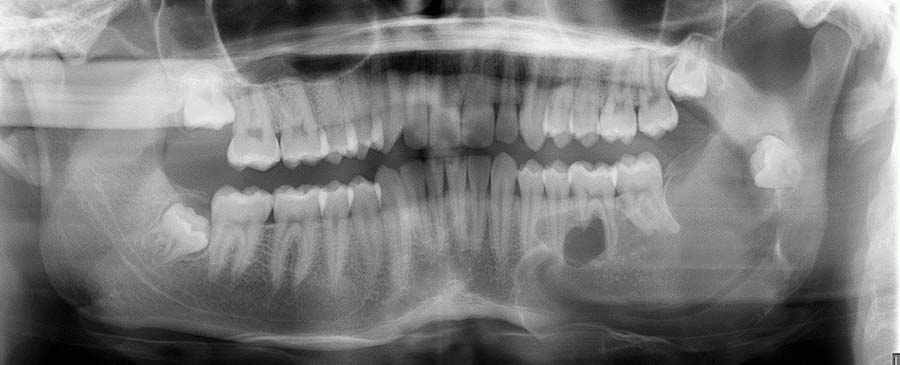

With more than 100 "jaw in a day" surgeries completed at UTMB, Dr. Marwan performed one on Laura Reitze in October of 2022 for squamous cell carcinoma of the mandibular alveolar ridge, which is an oral cancer.